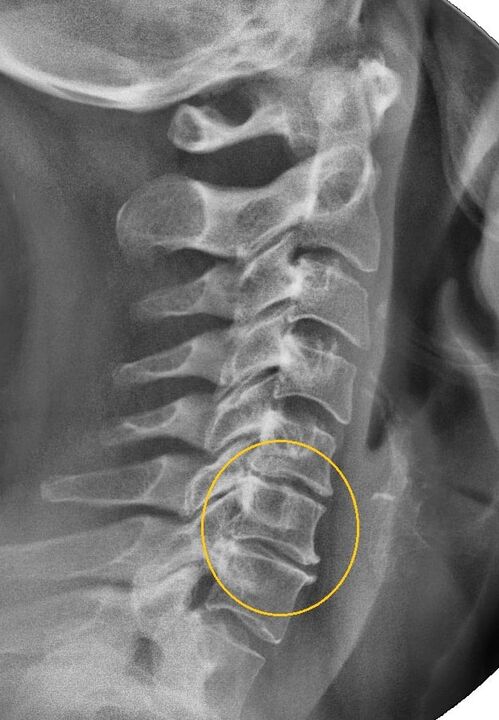

Najbolj informativen diagnostični postopek je radiografija. Patologije 1. stopnje ustrezajo 1. ali 2. radiološki stopnji. Nastale slike prikazujejo značilne znake bolezni.

| Rentgenske stopnje cervikalne osteohondroze 1. stopnje | Značilni znaki |

|---|---|

| 1. stopnja | Manjše spremembe v ukrivljenosti hrbtenice v vratnem predelu, ki prizadene enega ali več segmentov |

| 2. stopnja | Rahla zadebelitev medvretenčnih ploščic, deformacija uncinatnih izrastkov, izravnava lordoze, manjše rasti kostnih struktur. |